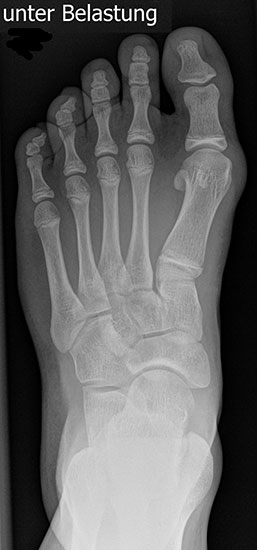

Röntgen

Standard ist die belastete Röntgenaufnahme des Fußes dorso-plantar und seitlich. Günstig ist eine Röhrenkippung von 10°-20°, um die Gelenke der Lisfranc-Linie einsehen zu können.

Ergänzend kann eine Schrägaufnahme hilfreich sein. Bei Metatarsalgien oder Pathologien der Sesambeine liefert die Sprinteraufnahme zusätzliche Informationen. Bei einer Pes planovalgus Fehlstellung wird ergänzend ein Saltzman view durchgeführt.

• Hallux valgus Winkel

• Hallux valgus interphalangeus Winkel

• Intermetatarsalwinkel I zu II

• Distaler Metatarsale Gelenkwinkel (PASA)

• Form des Mittelfußknochenkopfes

• Winkel Metatarsale I Basis zum Os cuneiforme mediale

• Metatarsalindex

• Elevation/ Plantarisierung I. Strahl

• Pes metatarsus adductus

• Wachstumsfugen

• Coalitiones

• Akzessorische Knochen